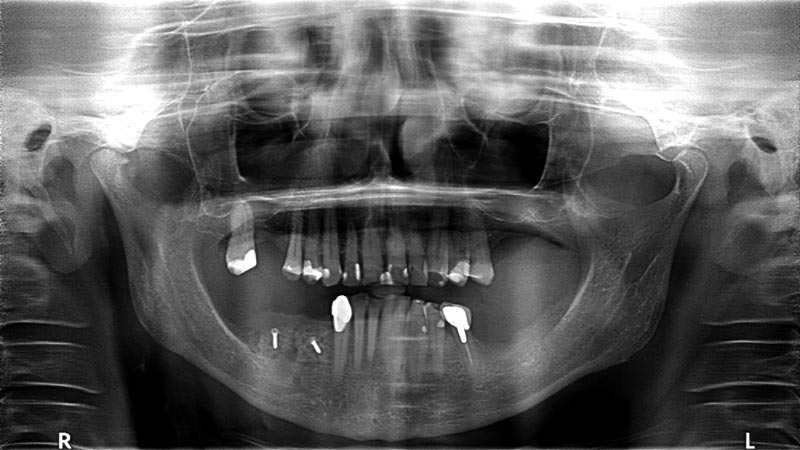

13/14 - Radiological situation 18 months post augmentation

Block augmentation with maxgraft® in the mandible - PD Dr. Dr. F. Kloss